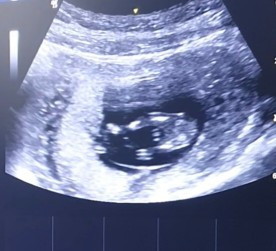

ช่วยทายเพศลูกจากภาพซาวด์หน่อยค่ะ อายุครรภ์ 12 สัปดาห์

หมอยังไม่ฟันธง เเม่ๆที่มีประสบการณ์คิดว่าจากภาพ น้องเพศ ช หรือ ญ คะ

น่าจะชายนะคะแม่

น่าจะชายนะคะ

คิดว่า ผช ค่า